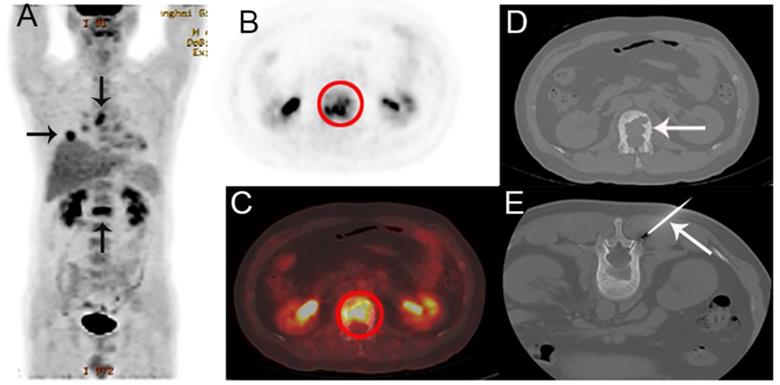

Figure 2

A 75-year-old man presented with hoarseness and hypochondriac pain, suspected of laryngocarcinoma with bone metastasis by PET/CT. A The coronal maximum intensity projection FDG PET image shows multiple FDG-avid lesions in the larynx, lung, extensive lesions in lymph nodes and multiple bone lesions. B,C The fusion images show FDG-avid lesions (SUVmax 13.6) in the larynx, lymph nodes and bone lesions. D,E The corresponding CT image of the 8th rib on the right hand side (D) and the biopsy under CT guidance (E).Histological examination confirmed that the bone lesion was bone tuberculosis, consistent with laryngeal histology.